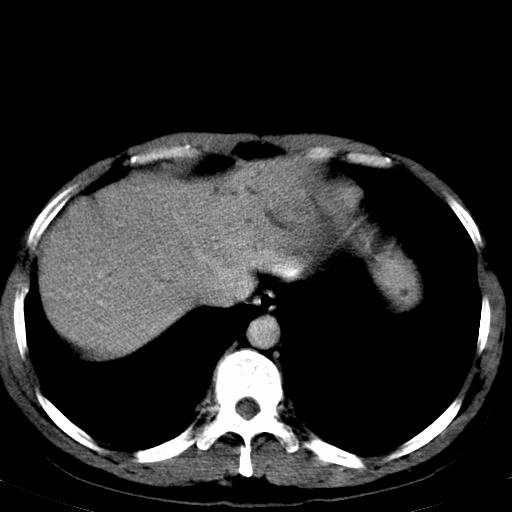

患者上腹部疼痛一月余,伴巩膜黄染;

实事求是的说,强化效果很一般,重点部位应重点观察,但有一点可以明确:肝门部胆管细胞癌。

考虑肝左叶胆管细胞癌侵犯肝门区并肝内胆管及肝总管扩张。

考虑肝左叶胆管细胞癌侵犯肝门区并肝内胆管及肝总管扩张、肝门淋巴结肿大。